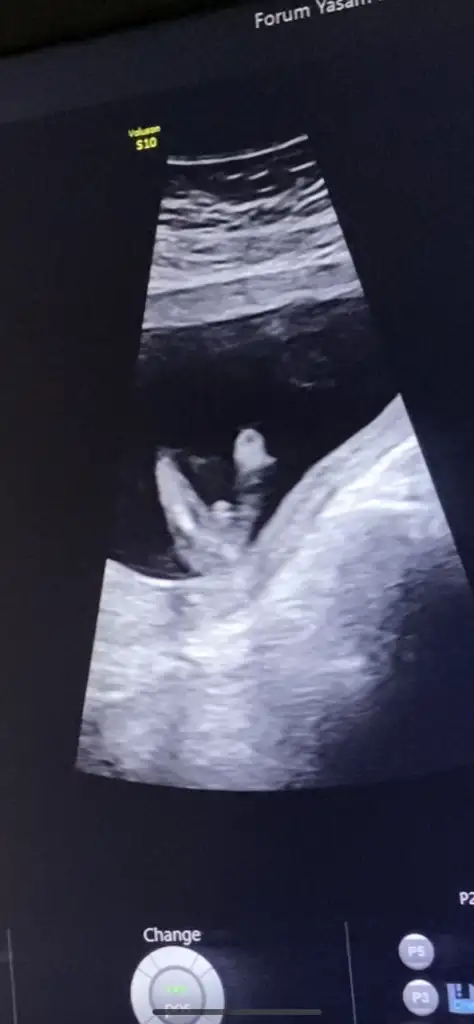

19 haftalık olduk hala doktora güvenemiyorum lütfen bakın anlayan söylesin çatlıcam meraktan.. bugün doktor randevum var 12.14 haftalar da hep erkek dedi 16. Haftada kız dedi güvenemedim 19 haftada da kız dedi yine güvenemedim çünkü pipi gibi bir şey var orda o nedir kızsa eğer ??? Anneler